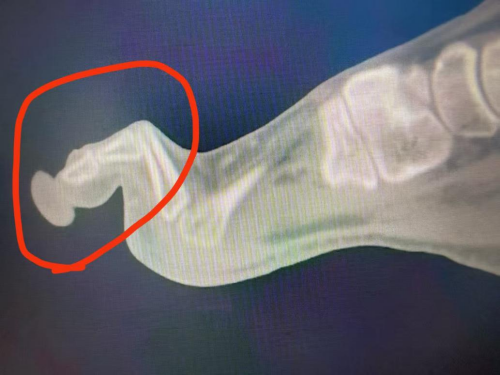

2025年9月,白力在长沙市中心医院内分泌科接受住院治疗。手足显微外科主任蒋亮东参与会诊后发现:白力不仅患有2型糖尿病,还合并右足第2、3趾锤状趾畸形,前足足底局部压力明显异常。蒋亮东解释,脚底就像一块每天都在承重的地面,如果某一个点长期承受过大的压力,时间久了,就容易先长出老茧,接着出现皮下损伤,最终发展成溃疡。白先生右足第2、3跖骨下方长期处于高压状态,这正是溃疡总在这个地方反复发作的重要原因,因为如果导致溃疡形成的高压点始终存在,溃疡即使表面长好了,一旦重新负重,仍然很容易再次裂开。

锤状趾畸形